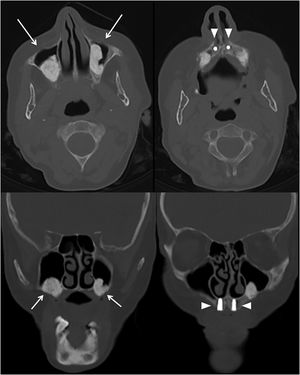

Mujer de 57 años, asintomática, que se estudió por hallazgo incidental de hipercalcemia moderada de 12,7mg/dL (valores de referencia: 8,5-10,5mg/dL) con paratohormona (PTH) dentro del rango de la normalidad. Tras el hallazgo de gammapatía monoclonal (inmunoglobulina IgG kappa 3,7g/L) de significado incierto, se realizó una TC de cuerpo entero para evaluar lesiones líticas sugestivas de mieloma múltiple o tumores paratiroideos, que fueron descartados. Sin embargo, se detectó una ocupación parcial de ambos senos maxilares por material amorfo sumamente hiperdenso (Unidades Hounsfield entre 1.300-1.700; figura 1, flechas). Dichas ocupaciones podían corresponder a cementomas de origen dentario, que fue descartado por la ausencia de cementación peri-implantes dentarios (fig. 1, puntas de flecha), o bien podían corresponder a cementomas fibrosos; la afectación por condrocalcinosis en rodillas reforzaba esta posibilidad. La paciente se sometió a un estudio genético que demostró la variante genética c.473G>C; p.(Gly158Ala) con heterocigosis en el gen receptor del calcio, lo cual es diagnóstico de hipercalcemia-hipocalciuria familiar, enfermedad genética con herencia autosómica dominante. Finalmente, la ocupación de los senos maxilares se atribuyó a la existencia de cementofibromas, tumores benignos muy infrecuentes que se originan en los huesos maxilares a partir de tejido fibroso, que se va osificando a lo largo de la vida. Aunque la fisiopatología es desconocida, el estado de hipercalcemia de la paciente podría haber favorecido la osificación de dichos fibromas.